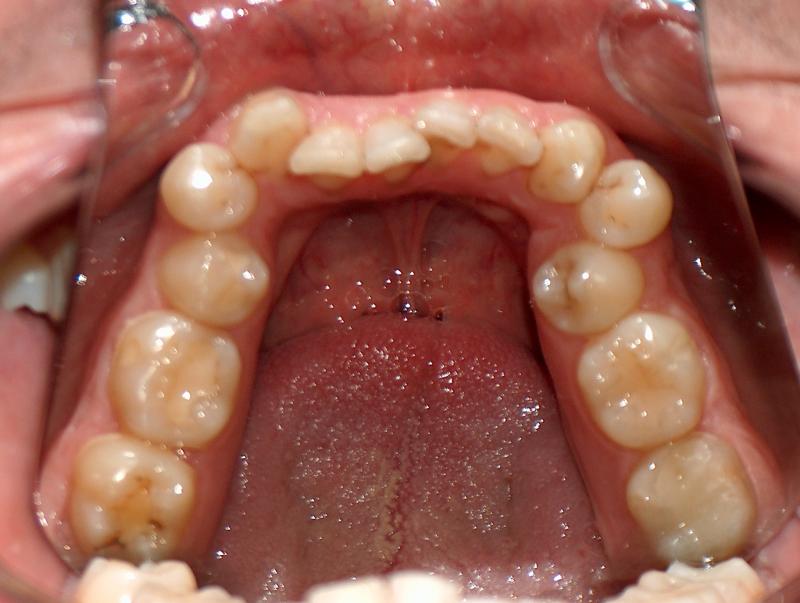

Steve N.

Invisalign Case

INVISALIGN, 16 months, 2 series of aligner to correct the anterior cross bite, to intrude the over erupted and extremely crowded lower incisors. COSMETIC DENTISTRY, leveling of incisal edges, gingival tissue contouring, and cosmetic bonding.

Cosmetic Dentistry, Mid-line Asymetry, Severe Crowding